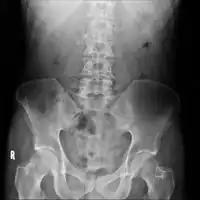

| Axial CT showing multiple calcifications in the pancreas in a patient with chronic pancreatitis | |

On CT scan, pancreatic and bile duct dilatation, atropy of pancreas, multiple calcifications of the pancreas, and enlargement of pancreatic glands can be found.[12]